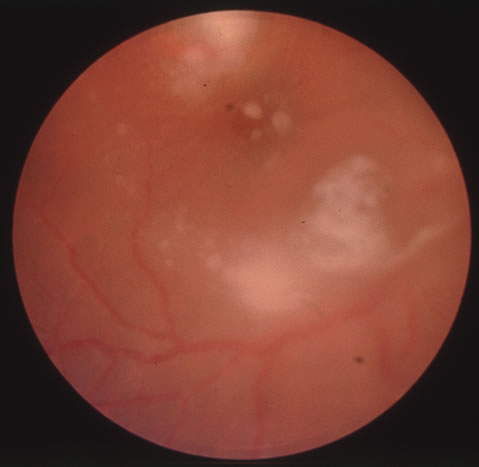

The acute retinal necrosis (ARN) syndrome is most often caused by the herpes zoster virus, although occasionally it may be a result of herpes simplex infection.12 It is typically described in healthy patients although association with immunosuppressed patients has also been described. Granular, nonhemorrhagic areas of retinal necrosis may be observed in the fundus, often rapidly coalescing with resulting blindness often caused by retinal detachment. There is often an associated vasculitis and vitritis. In immunocompromised patients VZV or HSV retinitis may also take the pattern of progressive outer retinal necrosis (PORN) (Fig. 6). PORN differs from ARN in that the former is multifocal, localized to the outer retina, and is less often associated with vasculitis and vitritis.

Fig. 6. Fundus lesions of progressive outer retinal necrosis (PORN). Note the multifocal lesions.